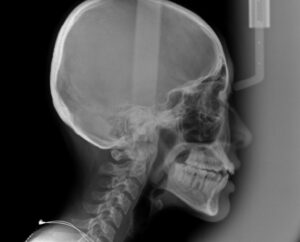

次にでっ歯さんの度合いを調べる

横からレントゲンのセファロを撮影

このデータをもとに

歯科医が治療計画を立てて